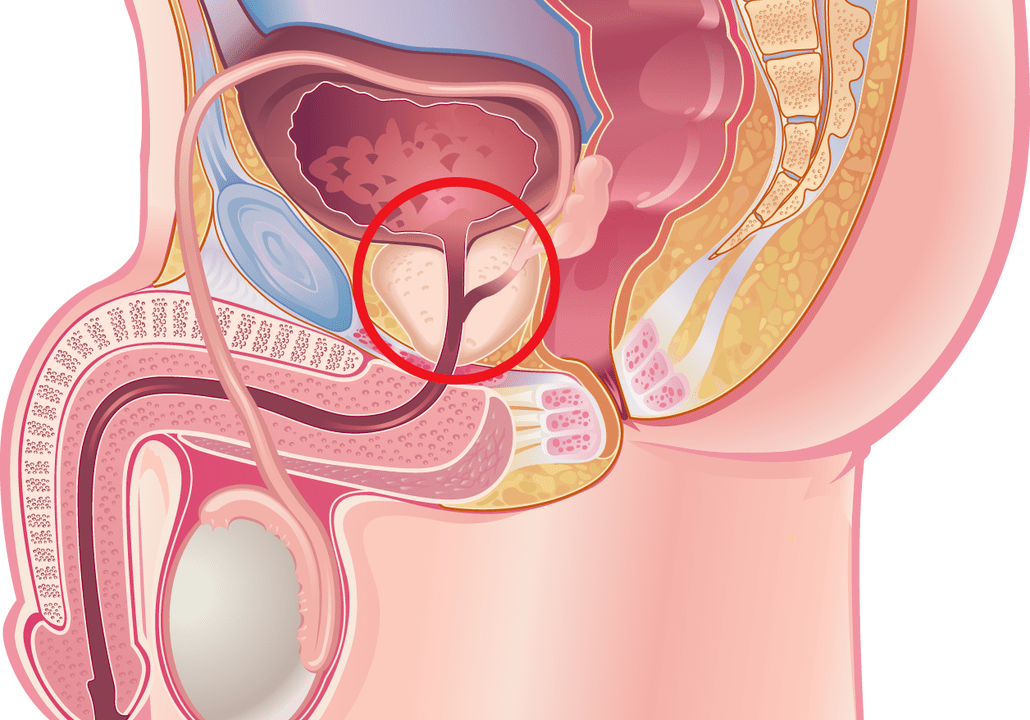

Viele Männer leiden unter Erkrankungen der Prostata. Liegt im Körper ein entzündlicher Prozess vor, der die Prostata betrifft, handelt es sich um eine Prostatitis. Die Konsultation eines Arztes kann durch die Verschreibung wirksamer Medikamente dazu beitragen, einer Reihe damit verbundener Komplikationen vorzubeugen.

Prostataentzündung

Prostatitis kann Männer über 20 überraschen. Um die Anzeichen einer Prostatitis rechtzeitig zu erkennen, ist es notwendig, sich mit ihren Symptomen vertraut zu machen, die von der Form der Krankheit abhängen: chronisch oder akut.